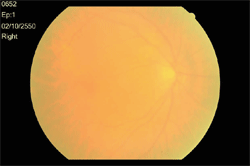

ภาพแสดงจอประสาทตาปรกติของตาซ้าย